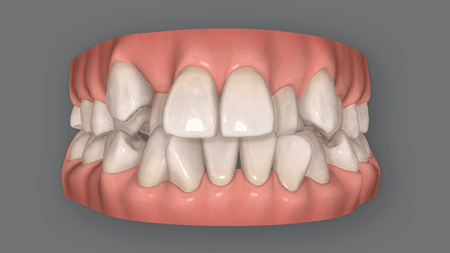

下あごが前にずれて受け口

口呼吸や噛み合わせの問題、あるいは遺伝的な要因で上あごに対して下あごが前にずれると、受け口になってしまいます。

下図のように、下あごが全体的に前に出てしまったため受け口になってしまった、という状態です。